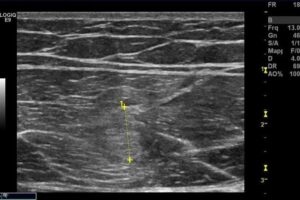

22.11.2011

In corrispondenza del terzo medio del muscolo retto femorale di sinistra si osserva area ipoecogena che misura in scansione trasversale mm.6,2.

In longitudinale si osserva distorsione dell’ecostruttura miofibrillare di medio grado.

Quadro compatibile con lesione muscolare distrattiva di 2° grado.

16.12.2011

In corrispondenza della zona precedentemente osservata si osserva la scomparsa del versamento e una completa ricomposizione dell’ecostruttura miofibrillare. Quadro compatibile con esiti di pregressa lesione muscolare distrattiva ormai stabilizzata.

Può iniziare attività sportiva (training differenziato).